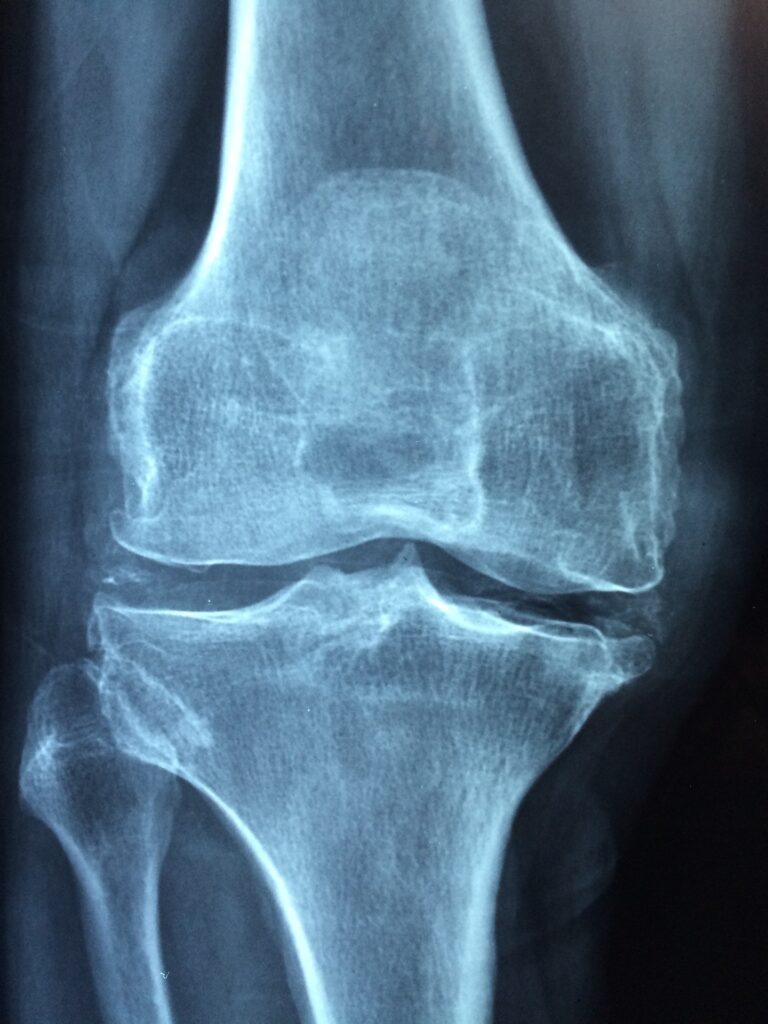

پوکی استخوان وضعیتی است که در آن استخوان های فرد تراکم و جرم خود را از دست میدهند و احتمال شکستگی استخوان ها افزایش مییابد.

نیمی از زنان بالای ۵۰ سال و از هر چهار مرد یک نفر در معرض خطر شکستگی استخوان قرار دارند. از دست دادن توده و تراکم استخوان میتواند در هر سنی رخ دهد. با این حال، پوکی استخوان در میان افراد مسن شایع تر است. پوکی استخوان بیشتر در زنان یائسه رخ میدهد.

استخوان های لگن، مهره های نخاعی و مچ دست شایع ترین محل شکستگی استخوان به دلیل پوکی استخوان هستند، اگرچه ممکن است در هر استخوانی رخ دهند. برای افراد مسن، شکستگی های لگن میتواند بسیار شدید باشد.